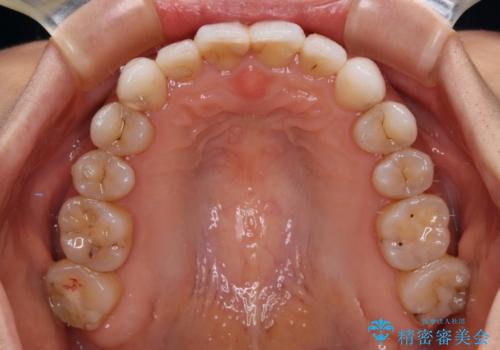

【モニター】開咬を治したい インビザラインによる矯正治療

- 上下前歯の開咬とデコボコを気にして来院された患者様です。

開咬(オープンバイト)はインビザラインによる矯正治療がワイヤー装置と比べて圧倒的に有利であるため、インビザラインによる矯正治療を行うこととしました。

通院されなかった時期があって治療期間が長くなったり、奥歯に抜歯が必要な歯があったりと、治療は一筋縄にはいきませんでしたが、何とか治療を終えることができました。

今後はインプラント治療やむし歯治療を進めて行く予定です。